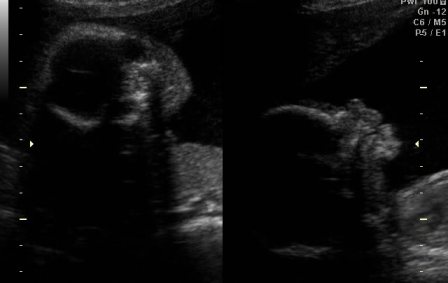

Rólunk! Voltunk a szúrás utáni kontroll UH-n, ami felért egy genetikai UH-nak, annyi mindent mértek, néztek meg. A gyerkőc, persze egyből széttárt lábakkal várt minket. Újabb megerősítés a fiúra. Méretei, szervei rendben.

És voltunk 4d-n is (a Várban, az ingyenesen. Köszi az infóért!) Szuper volt úgy is megnézni Őt. Apja szerint elég pisze orrú. Persze a keze neki is szinte végig a fejénél, az arca előtt volt, de azért 1-2 tiszta pillanat is volt.